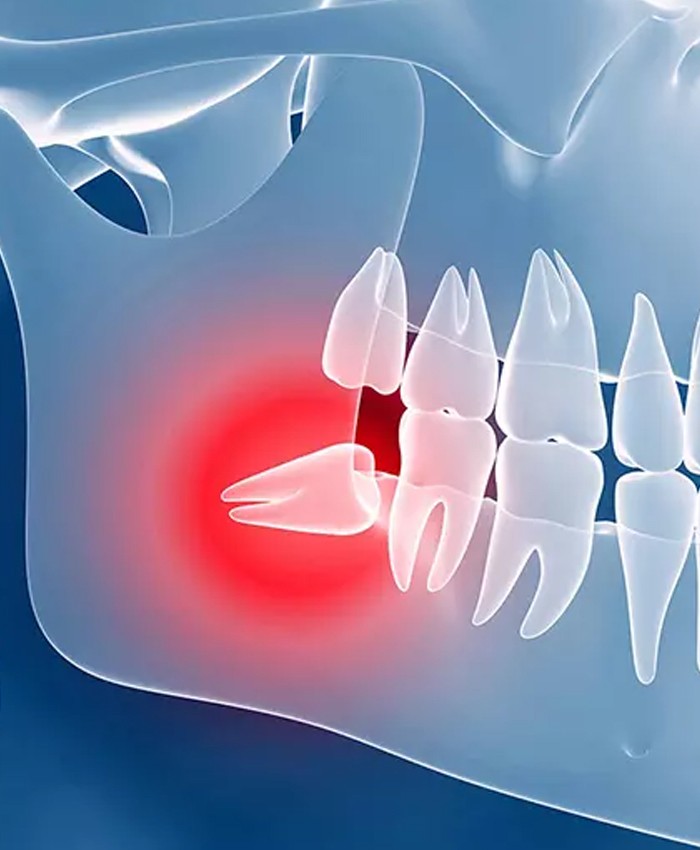

درد و ناراحتی ناشی از دندانهای نهفته شما را آزار میدهد؟

دندانهای نهفته، دردسرهایی جدی برای سلامت دهان و دندان به همراه دارند. ممکن است شما هم از دردهای شدید دندانها، احساس فشار و یا حتی عفونتهای مکرر رنج ببرید. اگر همچنان از جراحی دندان نهفته هراس دارید، بدانید که این فقط یک گام ساده است تا به راحتی از درد و مشکلات دندانی رها شوید.

چگونه تشخیص دهید که دندان شما نیاز به جراحی دارد؟

دندانهای نهفته معمولاً به دلیل عدم رویش کامل در فک یا فضاهای محدود در دهان، در زیر لثه گیر میکنند. علائمی مانند درد مزمن، التهاب لثه، ایجاد کیست یا عفونت، و یا فشار به دندانهای مجاور از جمله علائم دندان نهفته هستند.

چرا جراحی دندان نهفته باید انجام شود؟

دندانهای نهفته میتوانند باعث مشکلات متعددی مانند:

عفونتهای مکرر

درد شدید

ایجاد آسیب به دندانهای مجاور

به هم ریختگی ساختار دهان و فک